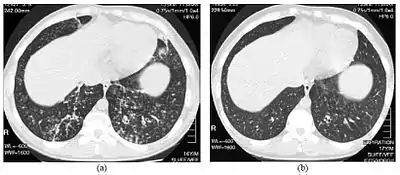

| High-resolution computed tomography images of the lower chest in a 16-year-old boy with diffuse panbronchiolitis | |

The diagnosis of DPB requires analysis of the lungs and bronchiolar tissues, which can require a lung biopsy, or the more preferred high resolution computed tomography (HRCT) scan of the lungs.[7] The diagnostic criteria include severe inflammation in all layers of the respiratory bronchioles and lung tissue lesions that appear as nodules within the terminal and respiratory bronchioles in both lungs.[4] The nodules in DPB appear as opaque lumps when viewed on X-rays of the lung, and can cause airway obstruction, which is evaluated by a pulmonary function test, or PFT.[6] Lung X-rays can also reveal dilation of the bronchiolar passages, another sign of DPB. HRCT scans often show blockages of some bronchiolar passages with mucus, which is referred to as the "tree-in-bud" pattern.[7] Hypoxemia, another sign of breathing difficulty, is revealed by measuring the oxygen and carbon dioxide content of the blood, using a blood test called arterial blood gas. Other findings observed with DPB include the proliferation of lymphocytes (white blood cells that fight infection), neutrophils, and foamy histiocytes (tissue macrophages) in the lung lining. Bacteria such as H. influenzae and P. aeruginosa are also detectable, with the latter becoming more prominent as the disease progresses.[4][5] The white blood, bacterial and other cellular content of the blood can be measured by taking a complete blood count (CBC). Elevated levels of IgG and IgA (classes of immunoglobulins) may be seen, as well as the presence of rheumatoid factor (an indicator of autoimmunity). Hemagglutination, a clumping of red blood cells in response to the presence of antibodies in the blood, may also occur. Neutrophils, beta-defensins, leukotrienes, and chemokines can also be detected in bronchoalveolar lavage fluid injected then removed from the bronchiolar airways of individuals with DPB, for evaluation.[4][9]